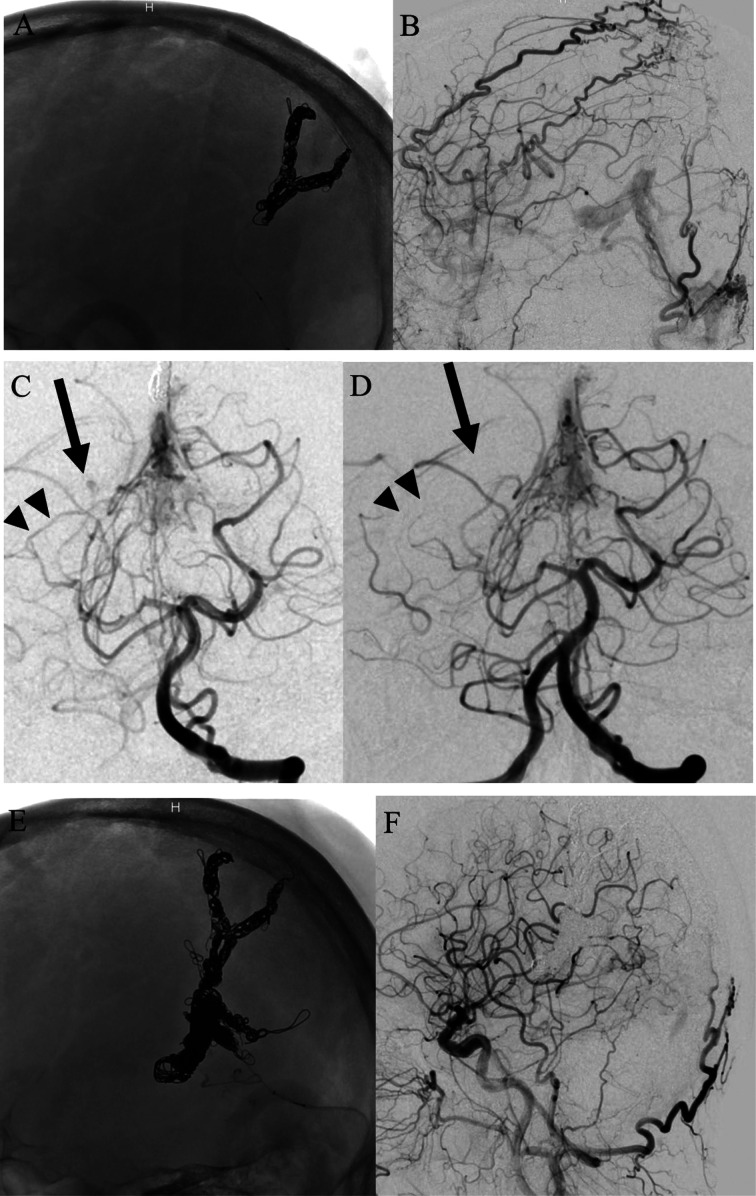

Objective: This report describes a rare case of a dural arteriovenous fistula of the falcine sinus associated with a flow-related aneurysm.

Patient and methods: A 68-year-old man presented with severe headache secondary to an intracranial hemorrhage. The bleeding was caused by a dural arteriovenous fistula (dAVF) of the falcine sinus with a flow-related aneurysm of the dural branch of the right posterior cerebral artery.

Results: Trans arterial obliteration of the aneurysm and its feeder using glue and trans venous embolization of the draining portions using a coil were successfully performed.

Conclusion: The unusual coexistence of a flow-related aneurysm on the feeder of the dAVF resulted in a unique hemorrhage.